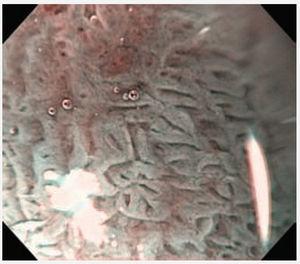

Paciente masculino de 55 años de edad, con enfer-fue sometido a mucosectomía endoscópica con medad por reflujo gastroesofágico. Se realizó pa-técnica de ligadura (figura 2). La endoscopia de nendoscopia, identificándose esófago de Barrett de control mostró tejido esofágico de características segmento largo. La cromoendoscopia digital con normales con signos de cicatrización en el sitio de imagen de banda estrecha (NBI) y magnificación, la mucosectomía (figura 3). El paciente continúa reveló zonas con un patrón tipo Pit IV de la clasi-en protocolo de vigilancia de displasia y con trataficación de Endo1 (figura 1). Las biopsias revelaron miento con inhibidor de bomba de protones. un foco de displasia de alto grado y el paciente

Figura 3. Endoscopia de control a los 2 meses, se observa mucosa esofágica normal en la zona de mucosectomía.